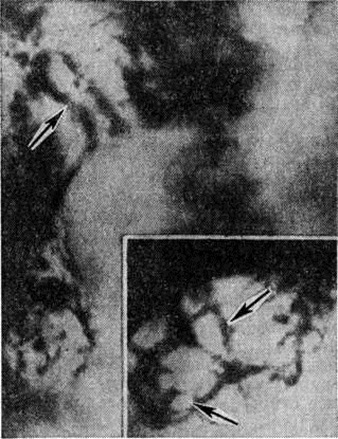

Микроскопически в костном мозге обнаруживается системное разрастание лимфоцитов. При обострении процесса наряду со зрелыми лимфоцитами выявляются пролимфоциты и лимфобласты. В костном мозге выделяют три типа инфильтрации: диффузную, диффузно-очаговую, очаговую. При первых двух типах инфильтрации расширенные полости костного мозга содержат значительное количество лимфоцитов, диффузно рассеянных в ткани или образующих наряду с этим компактные скопления (диффузно-очаговый тип). В отличие от других форм Лейкозы даже при массивной инфильтрации в костном мозге сохраняются небольшие очаги нормального кроветворения, не исчезают полностью жировые клетки. Для хронический лимфолейкоза характерно резкое рассасывание костной ткани и отсутствие признаков её новообразования. Данные прижизненного гистологический исследования костного мозга показывают, что очаговый тип инфильтрации наблюдается в ранние стадии заболевания. В отличие от лимфоидных узелков, выявляемых в норме в костном мозге, а также от реактивной нодулярной лимфоидной гиперплазии, сопутствующей ряду заболеваний, при хронический лимфолейкозе очаговые скопления лимфоцитов характеризуются довольно крупными размерами, лишены чётких границ, имеют тенденцию к слиянию, содержат наряду со зрелыми лимфоцитами пролимфоциты и лимфобласты. Разграничение этих изменений с метастазами в костный мозг лимфоцитарной лимфосаркомы ввиду сходности морфологический картины основывается на особенностях клинические, проявлений заболевания. При развёрнутой картине хронический лимфолейкоза в лимфатических, узлах обнаруживается диффузная инфильтрация ткани лимфоцитами с полным стиранием рисунка, которая может проникать через капсулу в окружающую жировую клетчатку. В селезёнке в некоторых случаях видны резко увеличенные в размерах фолликулы без центров размножения, сливающиеся друг с другом, однако чаще имеется полное стирание рисунка вследствие диффузной инфильтрации ткани лимфоцитами. Нередко встречаются поля склероза. В печени обширные скопления лимфатических, клеток располагаются главным образом в области портальных полей (рисунок 7), но могут встречаться и в синусоидных капиллярах. В зонах инфильтрации нередко имеет место разрастание аргирофильных и коллагеновых волокон. Часто наблюдается расширение желчных капилляров и застой желчи, дистрофия, частичный некробиоз и некроз гепатоцитов. В лёгких разрастания локализуются в стенках бронхов, что приводит к нарушению их дренажной функции и способствует развитию пневмоний. Могут наблюдаться участки массивной лейкозной инфильтрации ткани лёгкого. При микроскопии гнездные скопления лимфоцитов нередко обнаруживаются в строме почек, оболочках и мышце сердца, половых железах, жировой клетчатке и так далее. Очень редко встречается специфическая инфильтрация оболочек и вещества головного мозга. Частой находкой является скопление лимфоцитов в просветах сосудов различных органов, особенно при значительном лейкоцитозе. В отдельных случаях при обострении хронический лимфолейкоза возникают массивные опухолевые разрастания, исходящие главным образом из лимфатических, узлов. Опухолевые массы состоят из крупных недифференцированных клеток с уродливыми ядрами, нередко в них обнаруживаются участки некроза, кровоизлияния. Характерен резко выраженный инфильтрирующий рост.

Рис. 7. | ||